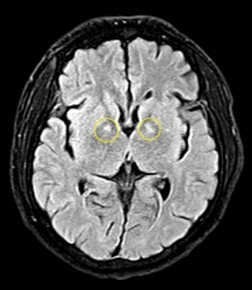

Hiện bệnh nhân nam có tổn thương não. Các bệnh nhân nữ tổn thương tim, suy tim, tiêu cơ tim và nguy cơ di chứng với tâm thần, thần kinh rất cao.

khi-co1.jpg

Hình ảnh tổn thương não của bệnh nhân nam - Ảnh BVCC